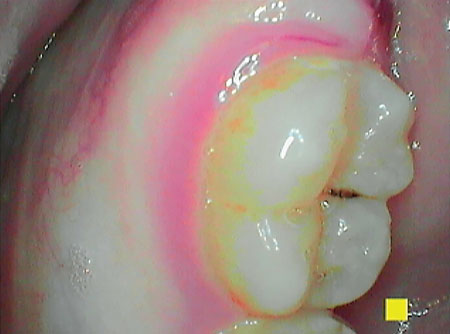

Perio mode allows the clinician to provide a more complete assessment of the patient’s oral health by rapidly assessing gingival inflammation, plaque, and calculus.2 Through the usage of LED lights, the camera demonstrates new plaque, which is shown as white, and the old plaque that is demonstrated in a yellow and orange shade.2

This allows patients to see the bacteria that was left behind even after their most recent brushing, which increases their need to change their oral health regime. The degree of gingival inflammation is detected with a light pink color to represent mild inflammation through a deep magenta to represent severe inflammation.2

In addition, the images allow the clinician to identify specific areas for the patient to improve on, and the images can be used document current oral conditions. The initial images can serve as a baseline to track improvements or progression of disease. Clinicians can praise the patients’ enhanced home care techniques during their preventive care appointments.